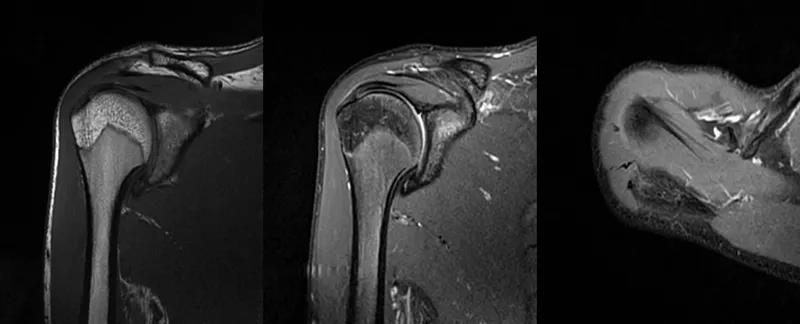

2、MRI检查MRI目前是诊断肩袖疾病中最常用的检查,可以直观的观察肩袖肌腱。

图21 斜冠状位(临床常用)a.T2,b.T1

图22 斜矢状位 a.冈上肌出口,肩袖诊断不如斜冠状位;b.冈上肌及肌腹脂肪浸润成度,评估手术与否

图23 横断位a.正常肩胛下肌;b.肩胛下肌损伤